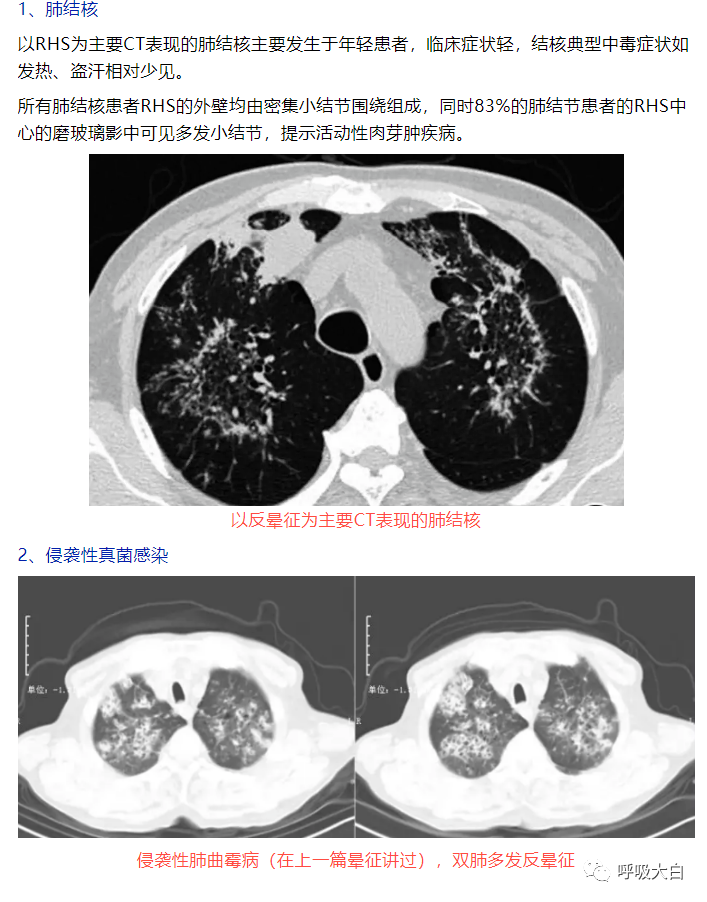

反晕征是一种特殊的胸部 CT征象,表现为环状高密度影围绕着中央密度较低的肺部阴影。起初认为,反晕征为隐源性机化性肺炎的特征性的征象;但此后被报道见于多种其他疾病,如肺副球孢子菌病、肺淋巴瘤样肉芽肿病、肺结节病、侵袭性肺真菌病、活动性肺结核及肉芽肿性多血管炎( 原韦格纳肉芽肿),亦可见于继发于感染或胶原血管病的机化性肺炎。

在隐源性机化性肺炎,反晕征中央的磨玻璃影的病理基础是肺泡间隔的炎症和细胞脱屑及少量终末气腔内的肉芽组织, 而外周的环状高密度影则对应远端气腔( 细支气管、肺泡管、肺泡腔) 内的纤维机化。表现为反晕征的结节病,外周的环状高密度影对应着多发的肉芽肿。肺隐球菌病则对应着肉芽肿性炎,PAS 染色可见着红色荚膜的隐球菌。肺结核的 CT环状高密度影对应的病理是上皮样肉芽肿,伴或不伴干酪样坏死,抗酸染色阳性或阴性。

在肉芽肿性疾病,其外围的环状高密度影不光滑, 而在非肉芽肿性疾病,外围的高密度影则较为光滑,此特征可用于初步判断病理性质。